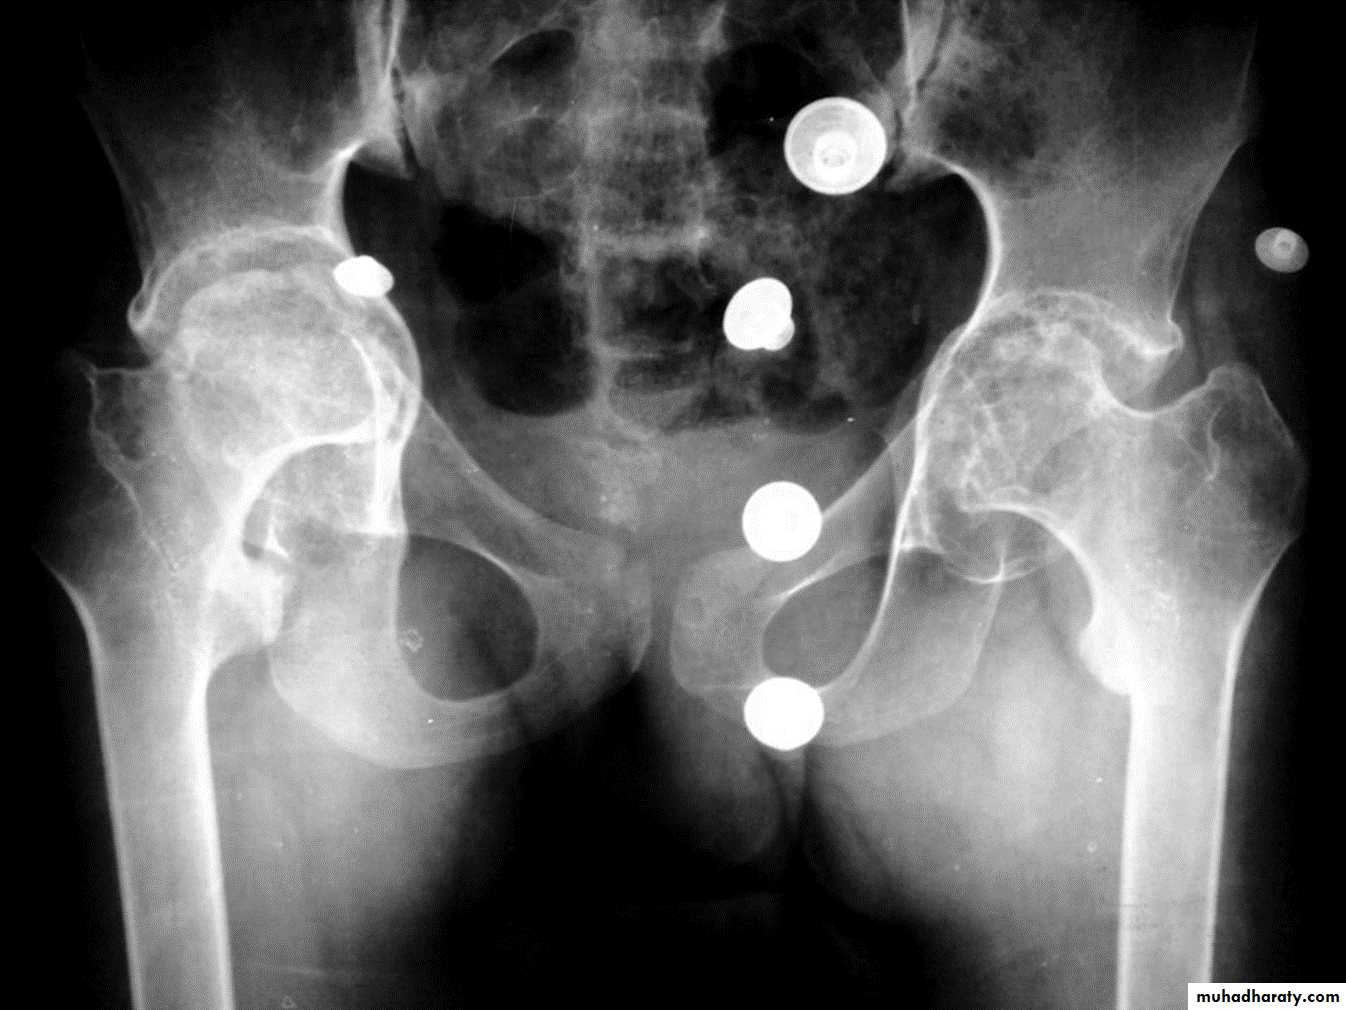

ANKYLOSING SPONDYLITIS (AS)

Seronegative spondyloarthropathy of the axial skeleton and proximal large joints.

Clinical: males >> females. HLA-B27 in 95%. Insiduous onset of back pain and stiffness. Onset: 20 years.Radiographic features:

* SI joint is the initial site of involvement:

bilateral, symmetrical

Erosions: early ,Sclerosis: intermediate , ankylosis: late

* Contiguous thoracolumbar involvement

Vertebral body "squaring": early osteitis

* Syndesmophytes

* Bamboo spine: late fusion and Bamboo spine

ligamentous ossification

*ankylosed spine (fracture)

* Enthesopathy is common(("whiskering of tuberosities )

* Arthritis of proximal joints (hip > shoulder) in 50% ,erosions and osteophytes